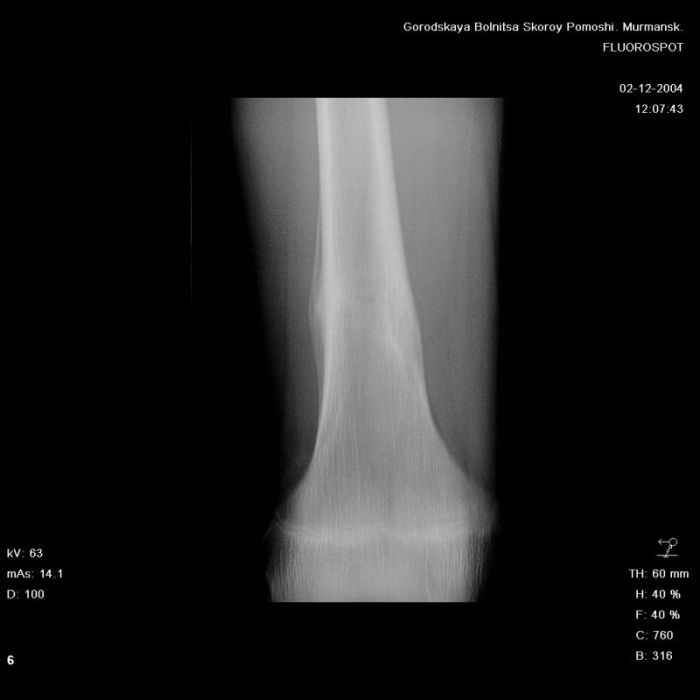

Здравствуйте, уважаемые коллеги!Представляю вашему вниманию интересный случай и пока что непонятный для меня в диагностическом плане. На днях в наше отделение (детской ортопедии и травматологии) поступил 13-летний мальчик по направлению из поликлиники с диагнозом: остеома нижней трети правого бедра.

Анамнез практически никакой: в следствие травмы (растяжение связок коленного сустава) от 07.11.2004 выполнены Rg-граммы в травмпункте и обнаружено опухолевидное образование. Первичные Rg-граммы я не публикую, так как они заметно худшего качества, да и динамики за прошедшие три недели не отражают. Болевой синдром купирован в течение трёх дней. В настоящий момент мальчика ничего не беспокоит. Ходьба не нарушена, опухоль пальпируется с трудом по задней поверхности в н\3 правого бедра, пальпация безболезненна, объем движений в суставах правой нижней конечности полный и симметричный. Кожа над опухолью не изменена.В нашей клинике проведено дополнительное обследование: общие анализы крови и мочи, биохимия крови без особенностей. Выполнены Rg-граммы на цифровом Siemens обычные и продольные томограммы срезами 3-5 мм, а также компьютерная томография поперечными срезами по 5 мм. Прошу обратить внимание, что на приведённых томограммах видны две полости 10х15 мм и 15х60 мм. Также имеются два опухолевидных образований наслаивающихся друг на друга: уплощённое и вытянутое 10х100 мм и элипсовидной формы 15х30 мм. Это хорошо заметно на фото a_1.jpg c_1.jpg и d_1.jpg. Плотность внутри полостей 125% от плотности костномозгового канала, плотность наружного опухолевидного образования 55% от плотности кортикального слоя. Также отмечается линия перелома по центру наружного опухолевидного образования.Исходя из полученных данных мнения в плане диагноза несколько разделились от 1)сочетания кортикальной фиброзной дисплазии и латентно протекавшего маршевого перелома н\3 правого бедра до 2)остеосаркомы. В отношении первого варианта не сходится отсутствие клиники при переломе такой крупной кости как бедро, второй вариант вообще оставлю без комментария, ибо некомпетентен. Хотелось бы услышать мнения коллег, с удовольствием ознакомлюсь с любыми предположениями и замечаниями.С уважением, Александр Е. КлоковОтделение детской ортопедии и травматологииБСМП г. Мурманска.

Структура области опухолевидного образования больше всего напоминала перестройку характерную для костной мозоли, никаких визуально инородных структур не выявлено.

С облегчением спешу сообщить, что гистологический анализ подтвердил сложившееся интраоперационно мнение, что мы имеем дело с посттравматической перестройкой костной ткани (костной мозолью). Плюс к этому фиброзные кортикальные дефекты. В обшем, зла нет и слава Богу.